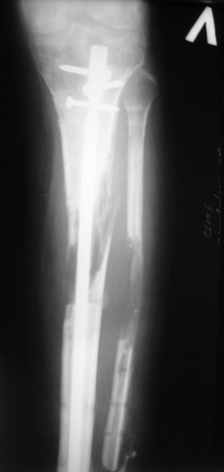

Больному выполнена резекция малоберцовой кости, ВХО раны, сближение отломков. Резекция м\б через отдельный разрез. После ВХО компрессия в аппарате, края раны сближены наводящими швами (без натяжения).

В случае гладкого заживления раны, при условии положительного решения вопроса с металлом, планируем перемонтаж аппарата Илизарова, дополнительную резекцию дистального отломка, выведение полокости голеностопного сустава в правильное положение (см. боковую Р-грамму), одномоментно остеотомия большеберцовой кости. После восстановления длинны голени, по всей видимости, артродез голеностопного сустава.

Рентгенограммы прилагаются. Фото местного статуса выложу в ближайшее время.

Я бы в похожей ситуации делал остеотомию малоберцовой кости на уровне перелома большеберцовой, как это сделал доктор ALEXEY. Ведь в верхней трети голени при остеотомии, и резекции особенно, высок риск повреждения малоберцового нерва или его крупных ветвей. А резекция на одном уровне с большеберцовой костью особых неприятностей не приносит ни во время операции ни после.

Еще один момент. При резекции костей голени на разных уровнях существенно затрудняется одномоментное укорочение и стыковка опилов большеберцовой кости, так как мешает натяжение неповрежденной межкостной мембраны между проксимльным отломком большеберцовой и дистальным отломком малоберцовой костей.